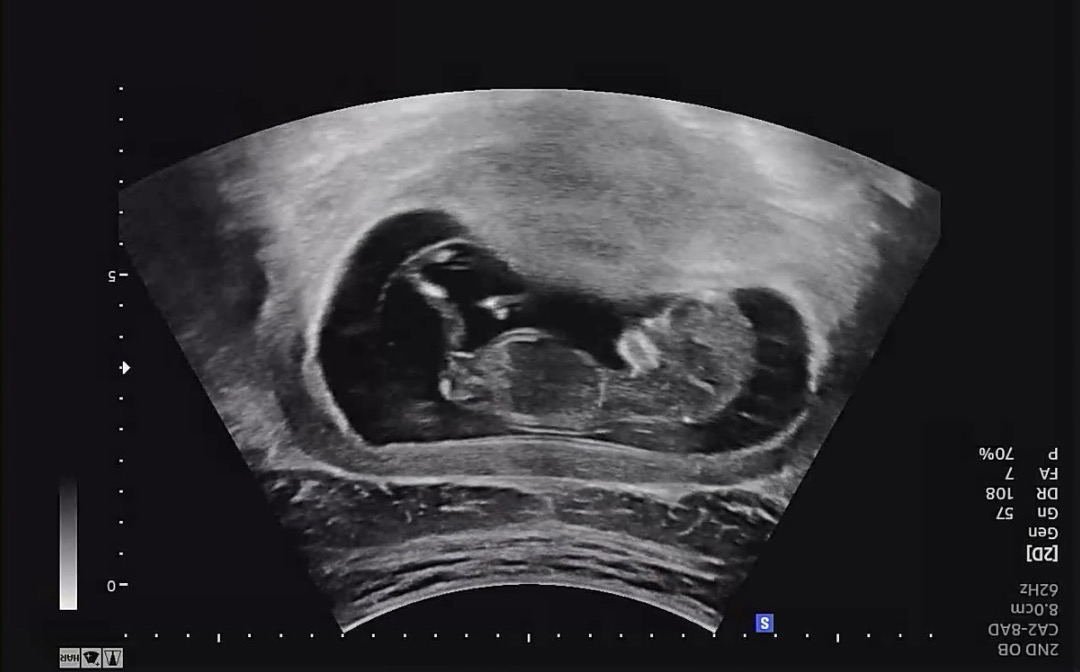

11주 2일차 각도법 봐주세요❤️

오늘 초음파보고왔는데 성별이 궁금해서!ㅎㅎ 각도법고수님들 아들일지 딸일지 한번씩만 봐주세요!😄